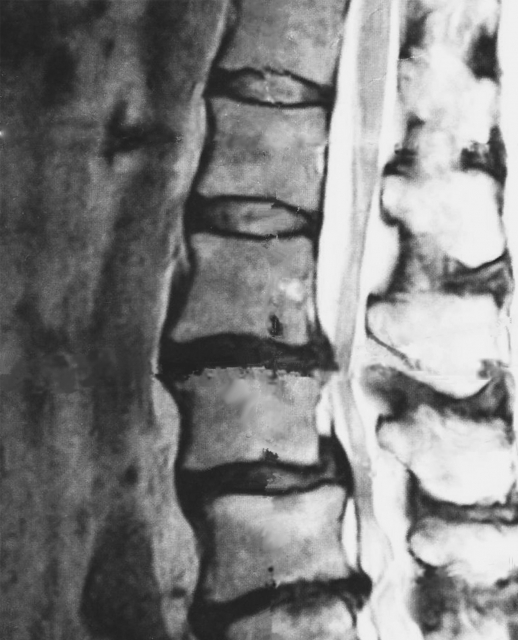

脊柱管狭窄症は背骨の中にある神経の通り道が狭くなり、神経や血管が圧迫されることで起こる疾患です。国内推定患者数は約240万人にのぼり、40歳以上人口の3.3%が悩んでいるとされています。

高齢社会に伴い患者数は急速に増加しており、最も特徴的な症状は間欠跛行と呼ばれる現象で、歩くと足やお尻に痛みやしびれが現れ、休むと症状が軽くなります。前かがみの姿勢では脊柱管が広がるため症状が楽になる一方、腰を伸ばすと狭窄が強くなり症状が悪化するのが特徴です。